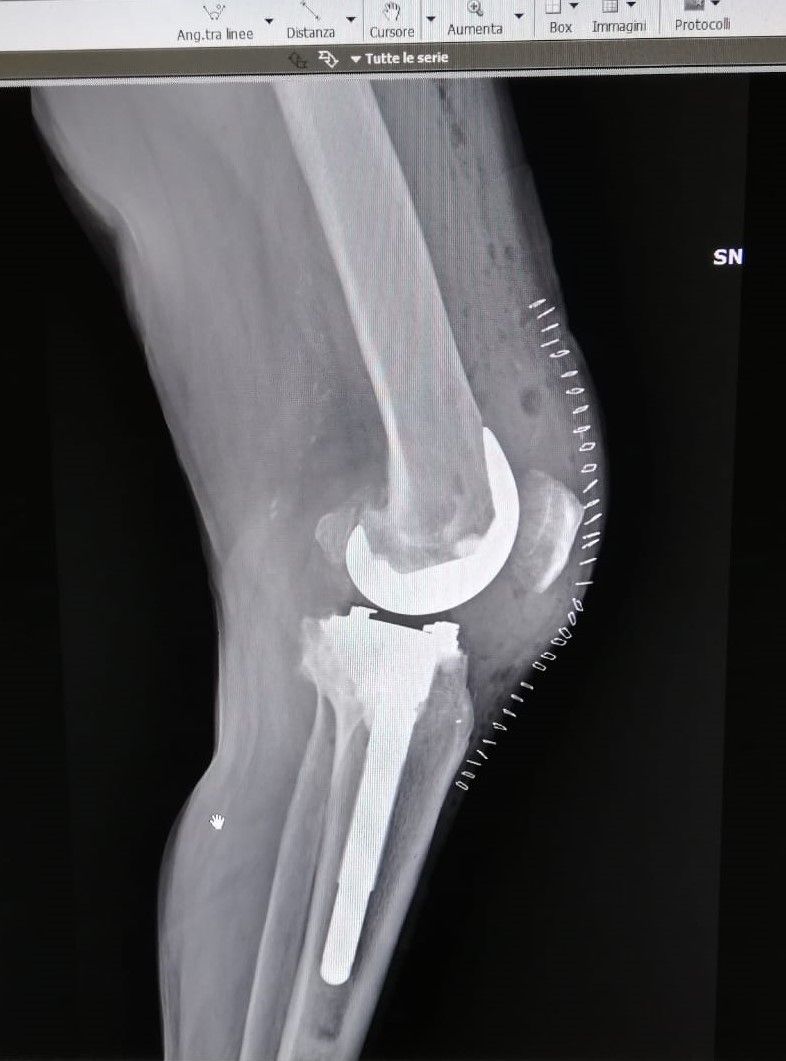

- protesi totale di ginocchio

- protesi mono-compartimentale del ginocchio

Dopo due anni di tentativi vani e aver consultato vari ortopedici, finalmente il dr.Zornetta mi ha illustrato bene la situazione del mio ginocchio. Persona che subito ti trasmette fiducia, competenza e finalmente ti spiega con chiarezza cosa hai, che dire e' una persona semplice e simpatica. Cosi' dopo gli ultimi esami mi ha consigliato l intervento al ginocchio con mezza protesi, mi sono fidata di lui anche perche' mi avrebbe operata lui stesso. A me e' andata tutto bene e lo ringrazio!

Medico competente e preparato, presente durante il ricovero e successivamente, nel mio caso protesi ginocchio. Disponibile e gentile. Esperienza positiva.

Il dottor Zornetta mi ha spiegato molto chiaramente tutti i punti che hanno portato alle operazioni per le protesi a entrambe le ginocchia. Presente anche nel post operazione. Sono molto contenta dei risultati e consiglio vivamente questo dottore.

Ottimo ortopedico,ti segue sino alla fine della operazione e oltre.quando hai bisogno,c'è.ho fatto 2 protesi ai ginocchi da lui.